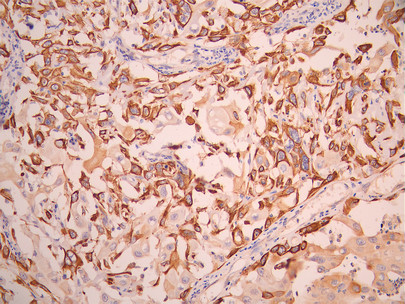

• IHC image of CSB-RA090368A0HU diluted at 1:100 and staining in paraffin-embedded human cervical cancer performed on a Leica BondTM system. After dewaxing and hydration, antigen retrieval was mediated by high pressure in a citrate buffer (pH 6.0). Section was blocked with 10% normal goat serum 30min at RT. Then primary antibody (1% BSA) was incubated at 4°C overnight. The primary is detected by a Goat anti-rabbit polymer IgG labeled by HRP and visualized using 0.05% DAB.